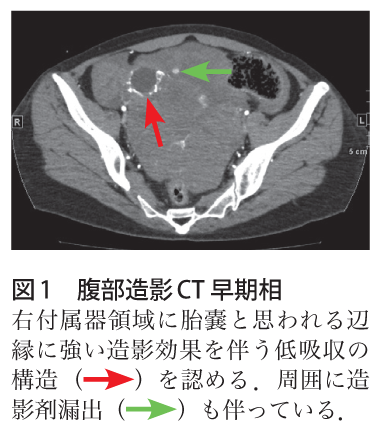

メトトレキサート単独投与による非観血的保存的治療が可能であった卵管間質部妊娠4症例 産婦人科の実際 70巻2号 医書 jp